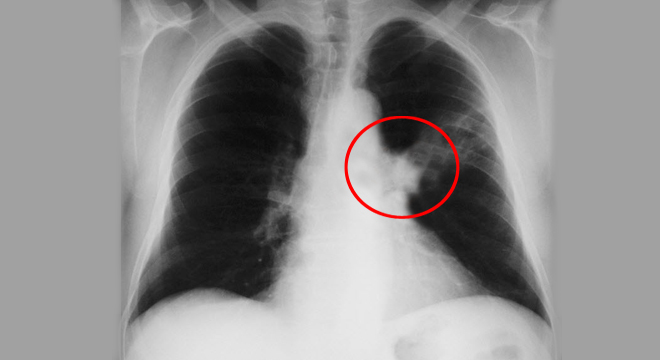

Lungenkrebs: Sichtbar im Röntgenbild

Zur Diagnose eine Lungenkrebses werden verschiedene Untersuchungen und Abklärungen durchgeführt. Dazu gehören unter anderem:

• Röntgenaufnahme der Lungen

Die genaue Diagnostik erlaubt es, das Stadium der Erkrankung zu beurteilen. Die Klassifikation erfolgt nach dem TNM-System; dabei werden die Grösse des Tumors, der Lymphknotenbefall und eventuelle Ableger (Metastasen) berücksichtigt.